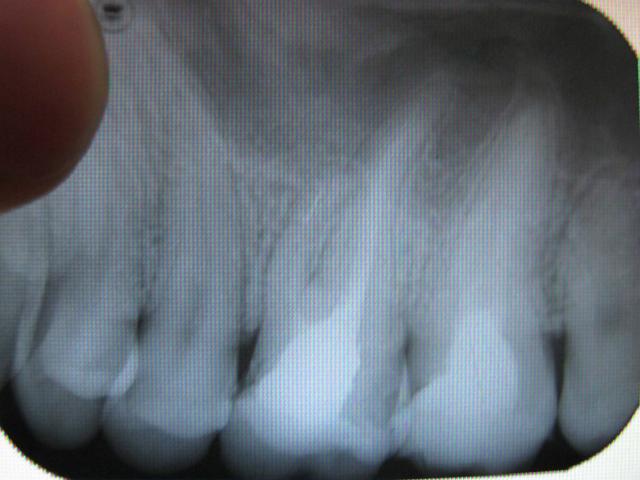

вот снимки.

сегодня зашол ещо к одному врачу он сказал что можно поставить коронку а если когда-нибуть заболит то прооперировать и вырезать это образование. А какие варианты лечения есть, кроме оперативных и есть ли они?? Спасибо.

Нда.... Такой отломок достать будет очень и очень сложно.

Нужно попробовать если уж не извлечь, то хотя бы обойти его. Если извлечь или обойти этот отломок не получится, то все остальные варианты не очень хороши в плане прогноза.

Да, отломок иглы. Образование - ерунда. Если канал удастся нормально вычистить, то это образовапние через несколько месяцев закроется.

И никто из этих "многие врачи" не соизволил вскрыть зуб и перелечить его? Отломок в канале не может не влиять. Нюансов много, но лучше перелечить этот зуб.

Кстати, семёрка рядом тоже не ахти.